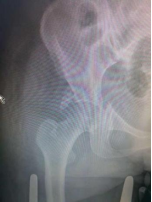

6.髋臼骨折